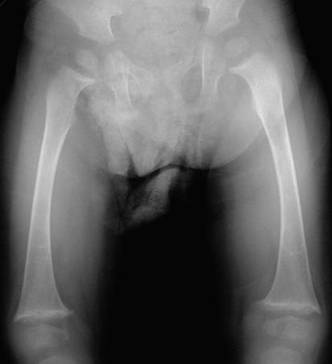

o شكل غير معتاد لعظام العمود الفقري حيث يكون لها شكل الفراشة butterfly vertebrae في 50% من الحالات

o الأشعة للعظام لمعرفة العيوب العظمية في العمود الفقري والأضلع والأطراف